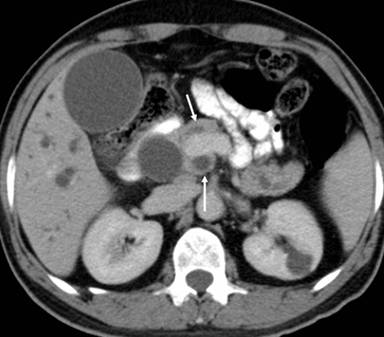

He underwent a pancreaticoduodenectomy. On transecting the neck of the pancreas, there was a small duct (4 mm) on the cut surface anterior to the portal vein. While dividing the bulky uncinate process, which seemed to extend posteriorly and to the left of the portal vein, a dilated duct (10 mm) was encountered. This dilated duct was found to be continuous with the main pancreatic duct posterior to the portal vein. The anterior duct in the neck of the pancreas terminated a few centimeters within the body of the pancreas without communication with the main pancreatic duct. The large pancreatic duct encountered in the uncinate process resection was closed with interrupted 5/0 polypropylene sutures. The neck of the pancreas anterior to the portal vein was excised up to the dilated main pancreatic duct, well to the left of the portal vein. The main pancreatic duct was laid open and a side to side pancreaticojejunostomy was performed. The patient made an uneventful recovery from the surgery. A review of the CT scan showed the double ducts encircling the portal vein with the main pancreatic duct lying posteriorly to the portal vein (Figures 1, 2, 3 and 4).

Figure 1. White arrows demonstrating the dual pancreatic ducts around the portal vein. |